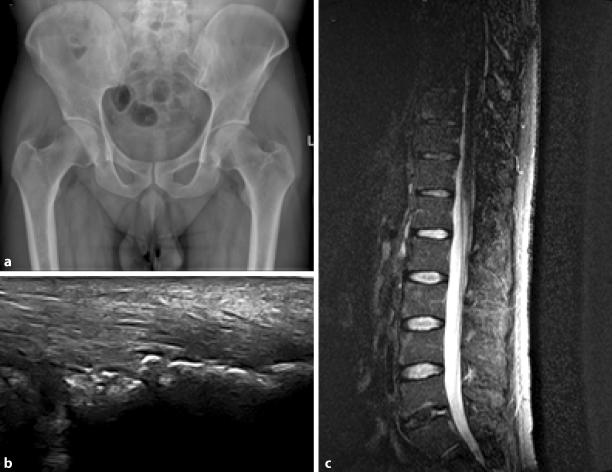

Bildgebung ist eine Schlüsselkomponente der Klassifikationskriterien für SpA, primär wegen des Fehlens spezifischer klinischer Symptome sowie der unterschiedliche Krankheitsaktivität im Laufe der Zeit. Beispielsweise ist aus diesem Grund eine radiographisch dokumentierte Sakroiliitis der wesentlichste Bestandteil der international akzeptierten modifizierten New-York-Kriterien für AS [3]. Jedoch kann das herkömmliche Röntgen nur die strukturellen Folgen der Entzündung visualisieren. In der letzten Dekade sind mehrere bildgebende Verfahren verfügbar geworden, die sowohl bei der Diagnose und Verlaufskontrolle von axSpA und pSpA als auch bei der Vorhersage der strukturellen Schäden und eventuell sogar bei der Vorhersage eines therapeutischen Ansprechens helfen können. Frühe entzündliche Veränderungen können mittels MRT, oft über mehrere Jahre, bevor das Auftreten von Sakroiliitis auf Röntgen festgestellt werden. Dementsprechend wurde MRT in der ASAS Klassifikationskriterien für axSpA sowie für pSpA eingebaut [1]. Weiters kann Ultraschall helfen, die klinisch schwer zu beurteilenden Enthesen zu untersuchen (Abb. 5).

Abb. 5

Bildgebende Verfahren in Spondylarthritis; a anteroposterioren Röntgenaufnahme des Beckens mit bilateraler Ankylose der Ilisosakralgelenke; b Enthesitis der Achilles-Sehne im Ultraschall mit Enthesophyten, Knochenerosionen, Bursitis und hypoechogene Sehnenstruktur; c sagittale Magnetresonanzbild mit STIR-Sequenz der Brust- und Lendenwirbelsäule mit Syndesmophyten und glänzende Ecken